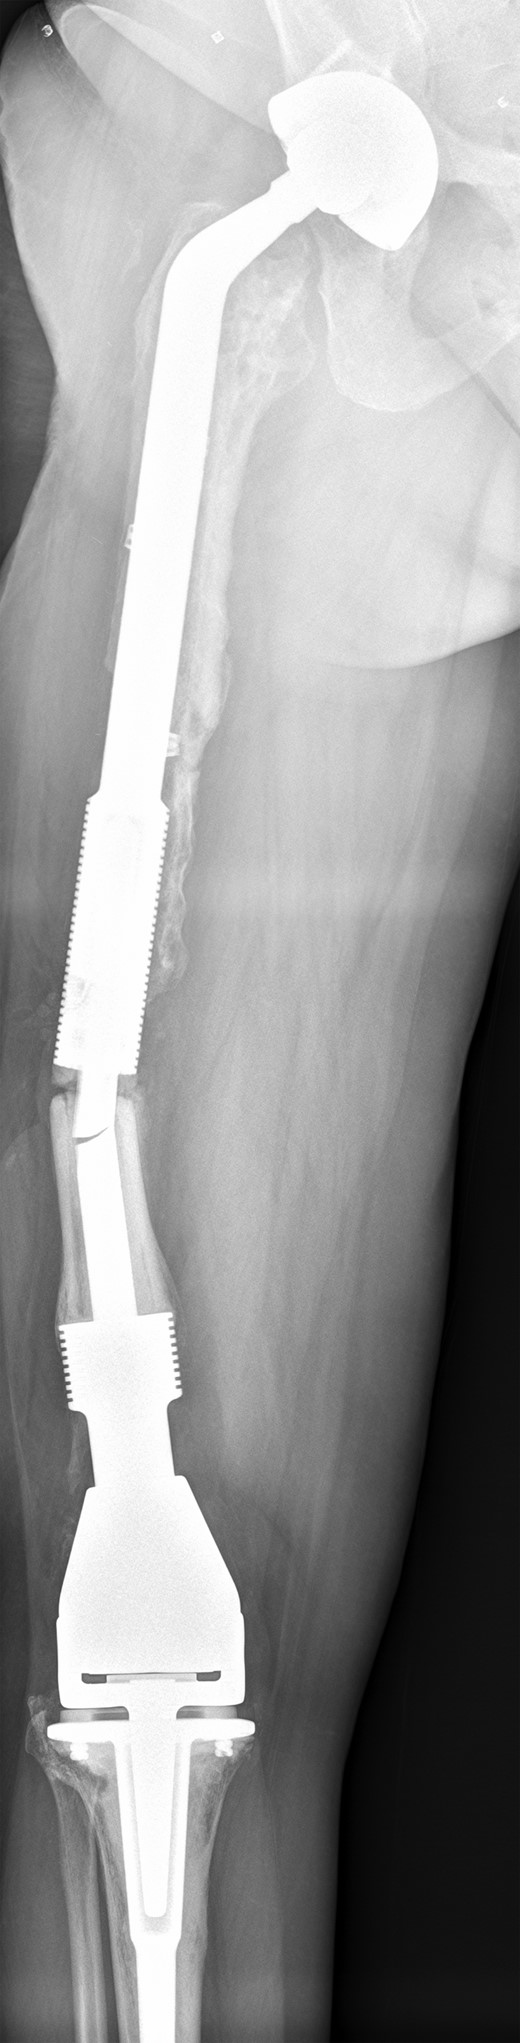

She remained well for 5 years, until she was referred back to our joint reconstruction unit due to a stress fracture in the stem of the distal femoral component, just below the junction with the cement-linked internal proximal femoral replacement (Fig. 5).

Full length femur radiograph illustrating fatigue fracture in stem of original distal femoral component.

After careful assessment of the radiographs and taking into consideration the complex nature of her failed salvage implant, a plan was made to design another custom-made component, this time a revision distal femoral prosthesis with a hollow cylindrical section to accept the existing, well-fixed salvage proximal femoral replacement.

The prosthesis was designed using preoperative long-leg calibrated measurement radiographs and manufactured using computer-aided design and computer-aided manufacture (CAD–CAM) techniques by Stanmore Implants Worldwide. The implant had a rotating hinge knee component and was made from a combination of hydroxyapatite-coated and silver (Agluna)-treated Cobalt–Chromium–Molybdenum (Co–Cr–Mo) and Titanium–6Alumunium–4Vanadium (Ti–6Al–4V) alloys.

The operation was carried out by the senior author and the customized distal femoral prosthesis was successfully cemented over the pre-existing internal proximal femoral replacement (Figs 6 and 7).